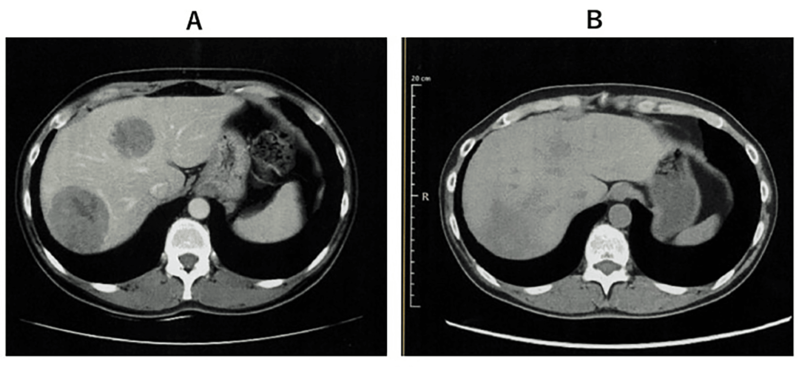

案例2:难治性宫颈癌转移灶消失,免疫功能恢复

小细胞未分化宫颈癌进展快、易耐药,预后极差。《Cureus》报道了一则突破性案例:一位 50 多岁的患者术后出现肝、淋巴结多处转移,化疗失败后,采用 WT1-DC 疫苗联合放疗: 1、第 67 天(注射第 5 剂疫苗后),CT 显示肝转移灶完全消失; 2、免疫指标(中性粒细胞 / 淋巴细胞比值等)恢复正常,原本因化疗受损的免疫功能显著改善。 案例3:胰腺癌患者中位生存期突破3年,7人成功手术 胰腺导管腺癌被称为 “癌王”,对放化疗天然耐药。《癌症免疫治疗杂志》的一项研究带来了新希望:10 例不可切除的胰腺导管腺癌患者(6 例 III 期局部晚期、3 例 IV 期转移性、1 例术后复发)采用 WT1-DC 疫苗联合化疗后: 1、所有患者肿瘤负荷下降,7人达到部分缓解,3人长期稳定; 2、9例患者中位无进展生存期 2.23 年,中位总生存期更是突破 3.52 年,远超传统治疗的预期。 3、 7 例成功接受了转化手术,其中 6 例实现 R0 切除(肿瘤完全切除,无残留),1 例为 R1 切除(镜下有残留)。 案例4:晚期十二指肠癌 4.3 年无进展,恶性腹水消失 十二指肠癌占胃肠道癌症的 0.3%-0.5%,虽发病率低但侵袭性强,易快速扩散,根治性手术是唯一可能治愈的手段,但晚期患者往往失去手术机会,且针对恶性腹水缺乏有效治疗方案。 《Cureus》曾报道一则案例:一位 72 岁的晚期十二指肠癌患者,腹膜播散伴恶性腹水,化疗失败后接受 WT1/MUC1-DC 疫苗联合细胞疗法: 1、第 8 次治疗后,恶性腹水消失,腹胀、水肿等症状消退; 2、原发病灶和转移淋巴结缩小,截至报道时,肿瘤 52 个月未进展,患者未出现严重副作用,且能正常活动。 锐赛EP-DC(医迪泰)是一种通用型的DC细胞疫苗,可靶向激活免疫系统对22种常见肿瘤抗原的免疫反应。产生强大免疫应答(CD4+/CD8+)识别所有肿瘤抗原,并覆盖广泛HLA类型。 当向患者给药时,医迪泰诱导的免疫应答有可能识别及破坏体内的癌细胞并向免疫系统持续提供支持和记忆,以便其能够持续靶向及预防癌症复发的可能。 2025年初,顶尖期刊Small Science(IF 12.7)发表了星空娱乐首席科学家范小勇教授与复旦大学附属上海市公共卫生临床中心研究组、南方科技大学附属深圳市第三人民医院/国家感染性疾病临床医学研究中心研究组的合作研究,题为“Dendritic Cell Vaccine Harboring Inactivated Mycobacteria Induces Immune Protection Against Tuberculosis in Murine Models and is Well Tolerated in Humans”。 本研究在上海市重大传染病和生物安全研究院官网的报道 该项临床研究使用了锐赛自主知识产权的新一代EP-DC疫苗技术。此前,这一创新技术已在多项抗肿瘤、抗HPV病毒治疗的临床研究中被证明有效。本次研究是EP-DC技术在结核病临床研究的重磅亮相。 星空娱乐负责制备DC 范小勇教授团队的突破性研究,首次证实DC细胞应用有望成为预防和治疗结核病的新策略。同时也揭示了新一代EP-DC疫苗技术可以在感染疾病的全病程治疗中发挥重大作用。 随着论文的发表,说明锐赛新一代EP-DC疫苗技术的应用场景已从肿瘤治疗的最后防线,扩展至疾病预防、病原微生物清除、病理进展逆转、疾病辅助治疗和术后防复发的全流程。